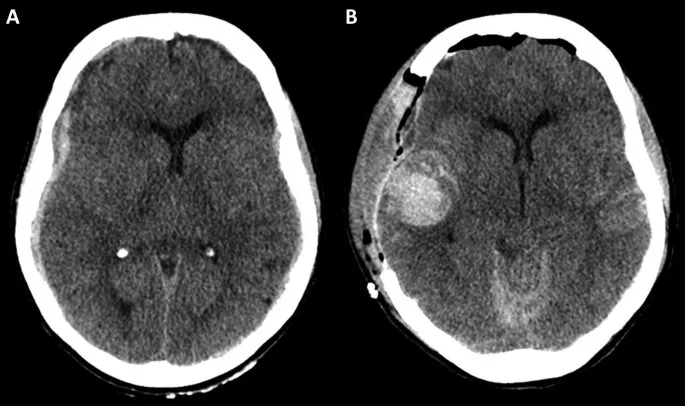

- Identifying Blood (Hounsfield Units):

- Acute blood: Hyperdense, +50 to +100 HU

- CSF: 0 HU; Brain: +20 to +40 HU

⭐ Non-contrast CT (NCCT) is the initial imaging of choice in acute pediatric head trauma due to its speed and sensitivity for fractures and acute hemorrhage.